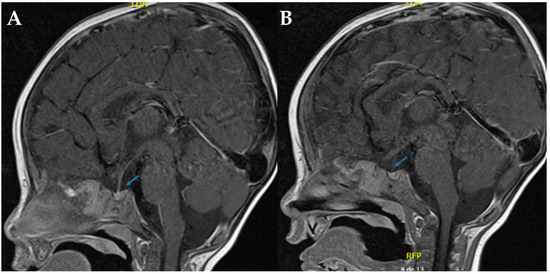

During hospitalization, the patient underwent clinical genetics evaluation and targeted massively parallel sequencing (next-generation sequencing, NGS) for diabetes insipidus-related genes (AQP2, AVP, and AVPR2) at the Department of Pathology and Laboratory Medicine of FVL. A novel homozygous missense variant, NM_000486.6:c.398T > A (p.Val133Glu), was identified in exon 2 of the AQP2 gene. According to the American College of Medical Genetics and Genomics (ACMG) criteria [1]—PM2 (absent from population databases), PP2 (missense variant in a gene with low benign variation), and PP3 (computational evidence suggesting a deleterious effect)—and following review by the FVL Medical Genetics Board, this variant was classified as likely pathogenic. It is consistent with the patient’s clinical phenotype of NDI. The variant has not been previously reported in the Human Gene Mutation Database (HGMD), NCBI ClinVar, gnomAD, or the 1000 Genomes Project. Sequencing Sanger confirmation was performed (see Figure 2). Segregation analysis in the parents could not be performed due to loss to follow-up for administrative and social reasons.

Figure 2. Sanger sequencing analysis shows a homozygous c.398T > A transition in the exon 2 of the AQP2 gene (Blue Line, middle). In the upper localization is the reference sequence. Below is the case sequence. Mutation Surveyor® was used for the bioinformatic analysis.